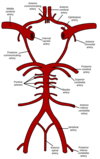

Course of Cerebral Arteries

ICA & VA pierce the dura and course in the subarachnoid space along with their branches. These branches penetrate into the brain parenchyma and as they do are surrounded by the tapered perivascular space (Virchow-Robbin) and the pia mater or BBB.

What are the primary blood supply to the brain

Internal Carotid (80%) - anterior circulation

Vertebrabasilar Arteries (20%) - posterior circulation

Branches of Internal Carotid Artery

- Opthalmic Artery

- Posterior Communicating Artery (PCoA)

- Anterior Cerebral Artery (ACA)

- Anterior Communicating Artery (ACoA)

- Middle Cerebral Artery (MCA)

- Anterior Choroidal Artery

Branches of Vertebral Arteries

Posterior Inferior Cerebral Artery (PICA)

Anterior Spinal Arteries

Branches of Basilar Artery

Anterior Inferior Cerebellar Artery (AICA)

Superior Cerebellar Artery

Posterior Cerebral Artery

Pontine Arteries

What arteries contribute to the Circle of Willis

- Internal Carotid A

- Anterior Cerebral A.

- Anterior Communicating A.

- Posterior Communicating A.

- Posterior Cerebral A.

Termination of the ICA, VA and the circle of Willis are located where

Subarachnoid space